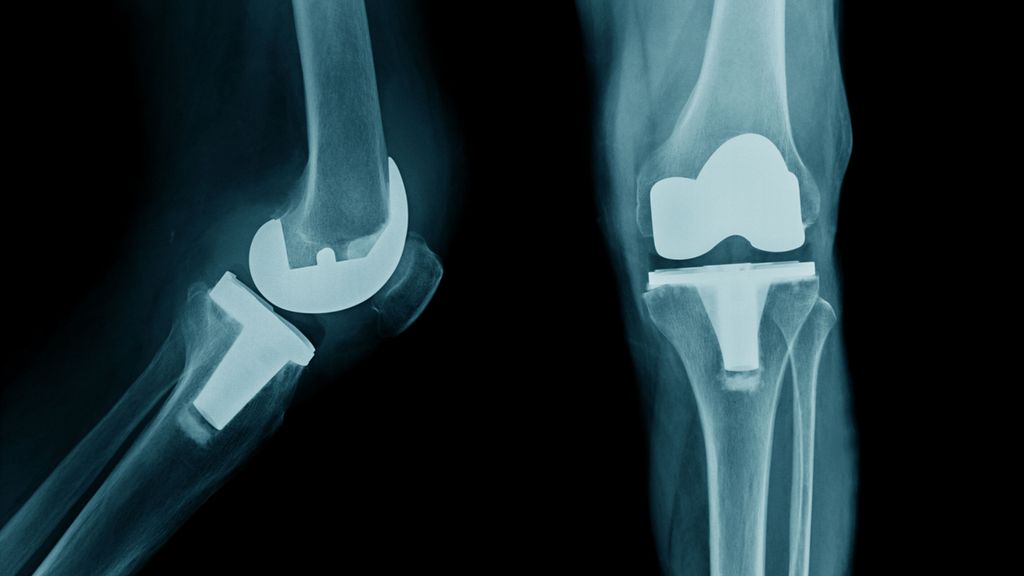

Die Herstellung eines symmetrischen Gangbilds sowie die Verbesserung der kinetischen und kinematischen Gangparameter im Gangzyklus stellen das Hauptaugenmerk in der Behandlung von ...

Die periprothetische Infektion (PPI) stellt eine der gefürchtetsten Komplikationen im Bereich der Orthopädie und Traumatologie dar. Sie ist verbunden mit hohen Morbiditäts- und ...

Knorpeldefekte im Knie können die Lebensqualität einschränken und langfristig zu Arthrose und der Notwendigkeit eines Gelenkersatzes führen. Es gibt diverse Behandlungstechniken, aber ...

Luxationen des Kniegelenks sind sehr seltene, aber schwerwiegende Verletzungen, die häufig mit Komplikationen einhergehen und unbehandelt zu schweren Instabilitäten im Knie führen können ...